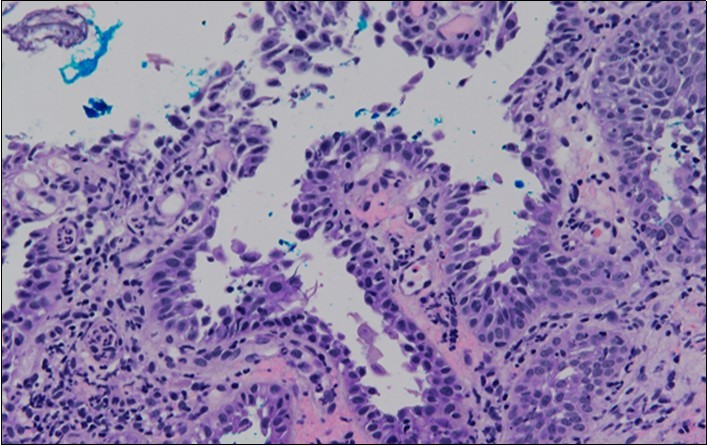

HPV test was negative for high risk subtypes of HPV. The punch biopsy specimen comprised a piece of inflamed cervical tissue in which the transformation zone was represented. The cervical tissue was covered by metaplastic and hyperplastic squamous epithelium showing intraepidermal suprabasal blister formation with acantholysis. Well vascularised dermal papillae lined residual basal cells giving rise to a tombstone appearance were present. There was no evidence of HPV, CIN, CGIN or invasive malignancy.

She was discussed at the hospital cyto-pathology conference to clarify the diagnosis. The original cytological smear specimen was reviewed, with features of bi-nucleation and koilocytosis consistent with LSIL. The cervical biopsy was also reviewed, confirming typical features suggestive of cervical pemphigus. (Figure 4a, Figure 4b, Figure 4c)

Figure 4a.Cervical tissue showing intraepidermal and supra-basal blister formation.

Figure 4c.Well vascularised dermal papillae with residual basal layer giving rise to tombstone appearance